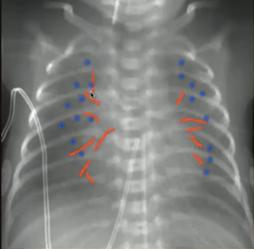

Example 1 主诉:30周早产儿出生后呼吸困难

胸片特点:气管插管;弥漫白色“铅笔尖”样白色小点。

诊断:新生儿呼吸窘迫综合症(表面活性物质缺乏症/透明膜疾病):是早产儿呼吸困难最常见的原因。

图5.新生儿呼吸窘迫综合症Example 2 主诉:足月儿剖宫产出生后出现呼吸困难